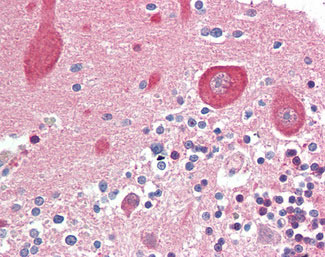

Anti-MAP2K1 / MEK1 antibody IHC of human brain, cerebellum.